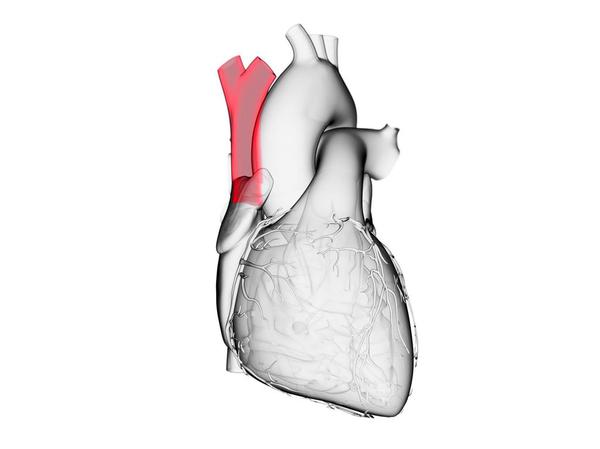

The Anatomy of the Coronary Sinus

The coronary sinus is a large vein that that returns deoxygenated blood from the heart muscle to the right side of the heart so that it can be replenished with oxygen.

The coronary sinus is located on the heart’s posterior (behind) surface and is positioned between the left ventricle and the left atrium. All mammals, including humans, are known to have a coronary sinus.

The length of the coronary sinus is from 15 to 65 millimeters (0.59 to 2.5 inches). It is wider than most of the coronary vei